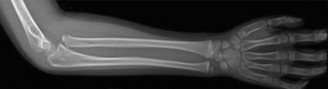

The correct answer is (B). Obtaining x-rays of the ipsilateral forearm would be the next step for evaluation of this child. She has an obvious radial head dislocation. Isolated radial head dislocations are thought to not happen in children—they are usually associated with an injury to the ulna which can be a very subtle ulnar bow. Failure to recognize the ulna deformity can compromise the success of any attempt at radiocapitellar joint reduction—the ulna often has to be corrected via an osteotomy to allow for the radiocapitellar joint reduction. A full forearm x-ray on this patient confirmed that there was a subtle ulnar bow relative to a straight line drawn down the x-ray (Fig. 10–8).

Figure 10–8 Objectives: Did you learn...? The importance of checking the radiocapitellar alignment on every pediatric elbow x-ray?